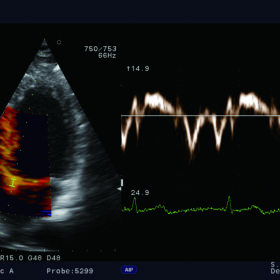

The Free Angular M-mode (FAM*) can be implemented in real time or reconstructed from the cine memory. Orientation at arbitrary angles allows for variation position. Whereas blood flow mapping with eFLOW allows demonstration of vascularity with high spatial resolution and minimal blooming.

In addition, the real-time, simultaneous side-by-side display of the B-mode and Flow image enable easy anatomical understanding in vascular examinations such as the carotid artery or lower extremities (Dual Dynamic Display – DDD).

| Doppler | CW Color Doppler, PW Color Doppler, Real-time Doppler Auto Trace |

| Καρδιακές λειτουργίες | ECG module, FAM (Free Angular M-mode), Tissue Doppler Imaging (TDI) |

Aloka UST-5299 Cardiac Phased Array